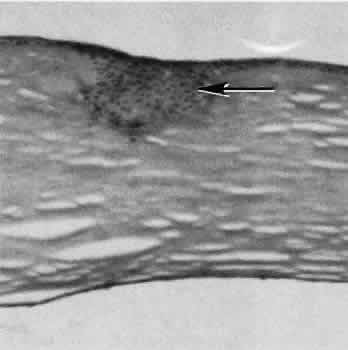

Proliferation and fibrous metaplasia of the lens capsular epithelium (Fig. 11) may close small rents through the lens capsule. After maturation of the fibrous tissue, the most superficial epithelial cells will form a new lens capsule. Most wounds to the lens, small and large, result in cataracts. Small wounds, however, may result in tiny focal opacities.38–39 Lens epithelial cells undergo fibromyoblastictransformation when stimulated by injury. The transformed cells are able to produce type I and type III collagen and glycosaminoglycans.40 This is the fundamental process resulting in opacification of the posterior lens capsule after extracapsular cataract extraction or phacoemulsification.41 Apoptosis (programmed cell death) also plays a role in the formation of secondary cataracts.42

Fig. 11. Light micrograph of a small rent in the capsule of a crystalline lens caused by a needle tip. A small wound such as this may heal leaving only focal opacification. Generalized lens opacification is the more common outcome of crystalline lens capsular damage. (Periodic acid-Schiff stain; × 100.)